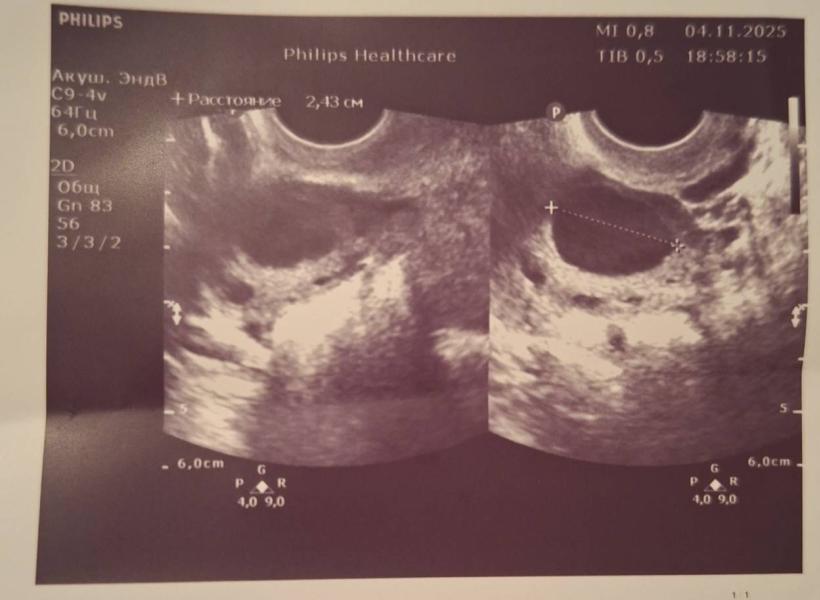

Что такое образование 24,3 мм на УЗИ: фолликул или киста

Может кто разбирается, это фолликул или киста или что это?

Написано образование 24,3мм